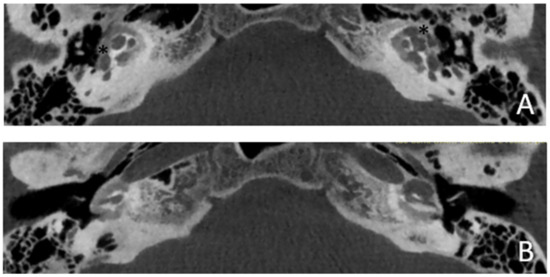

Patient #3, affected by otosclerosis: HL started as mild CHL, but she had a progression with a worsening of the bone threshold, probably due to cochlear evolution of the disorder. Even in this case, there was no indication for stapes surgery because of the communication between CSF and perilymph through the cavities. The images also show a superior semicircular canal deiscence (SSCD)on the left. CT and MR images show the bilateral cavities (Figure 5 and Figure 6).

Figure 6. MR images of patient #3 with otosclerosis and SSC dehiscence on the left side. MR cisternography: (A,B), axial plane. Note the fluid-signal in the newly formed cavity (white asterisk).